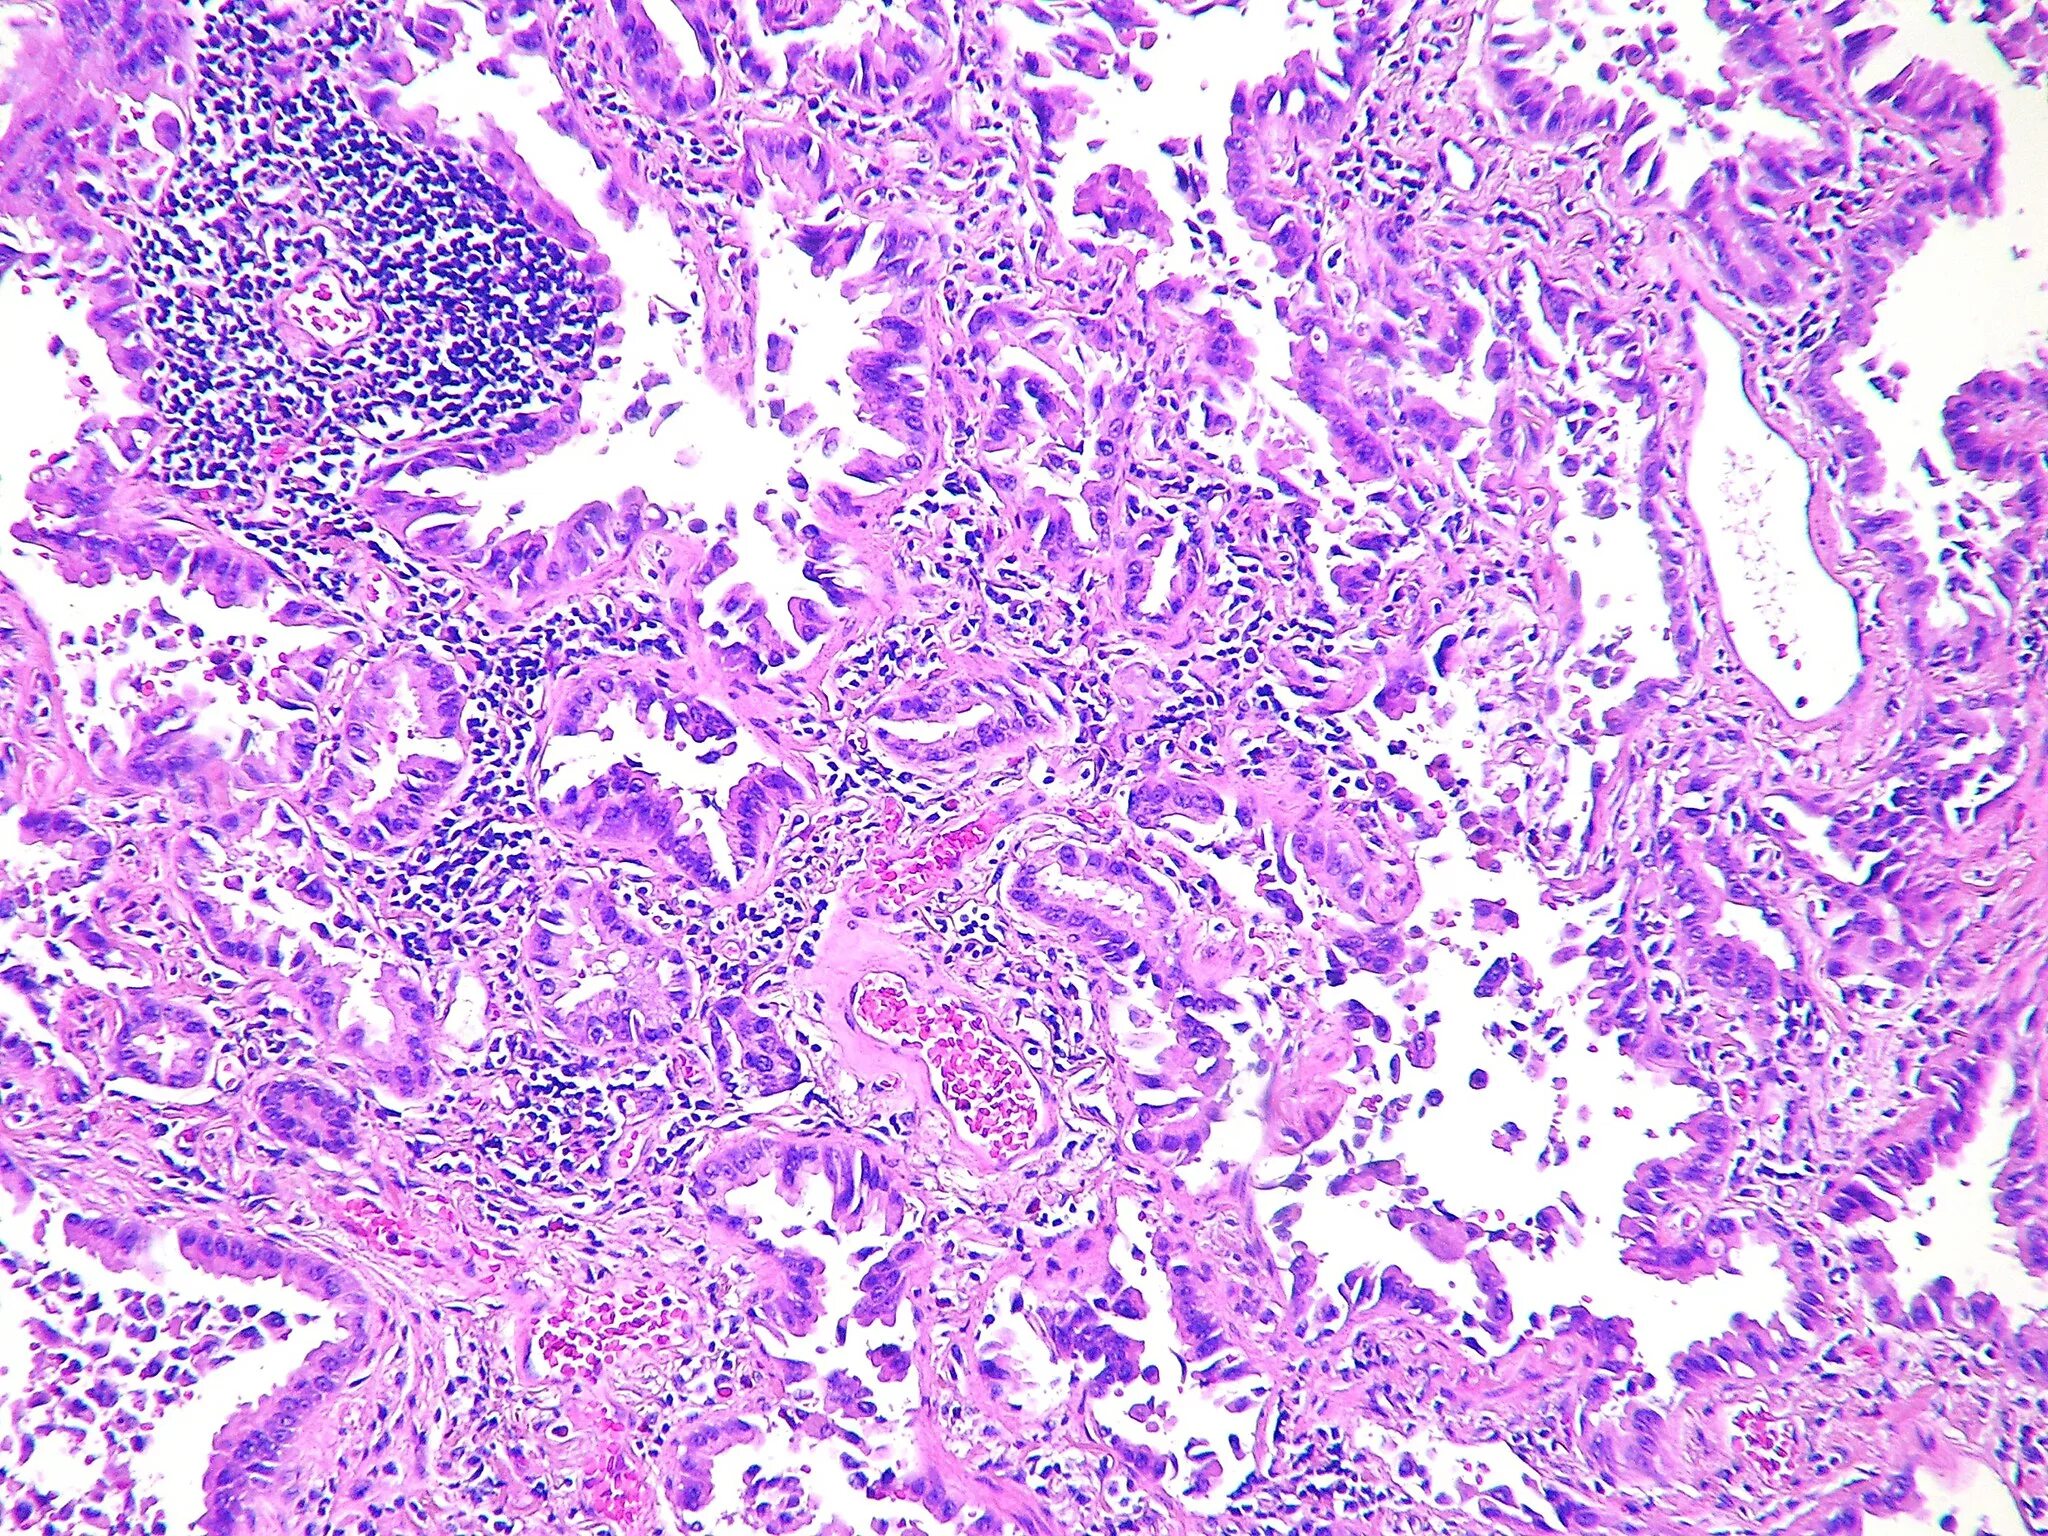

Что значит умеренно дифференцированная аденокарцинома